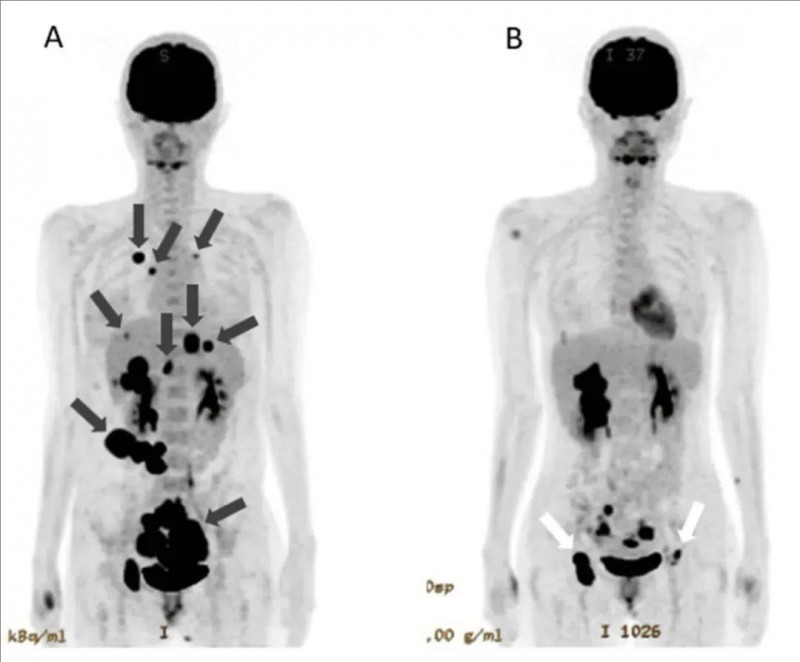

值得一提的是,其中一位卵巢子宫内膜样癌患者,此前接受过包括化疗、PARP抑制剂在内的5种全身治疗均不理想,入组接受GC203 TIL细胞回输后,影像学显示:肝脏及肺部转移病灶明显缩小,肿瘤靶病灶缩小66%(详见下图),最终达到部分缓解(PR)标准。

1、全身肿瘤明显缩小:治疗前全身PET-CT显示,该患者不仅存在原发性卵巢癌病灶,同时在肝脏、肺部、腹膜等多处出现转移灶。联合治疗后,原发性肿瘤明显缩小,肺转移灶及腹膜播散灶已消失不见,肝转移灶也显著缩小。